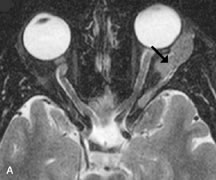

Fig. 18. A. T1-weighted, (B) T2-weighted fat-suppressed, and (C) T1-weighted fat-suppressed MR scans demonstrate a small dermoid cyst arising near the palpebral portion of the lacrinal gland (arrows). The lesion is similar in signal intensity to fat on the T1-weighted scan (A) consistent with a high adipose tissue content. The lesion shows fat-suppression and low signal intensity on the two fat-suppressed sequences (B and C) confirming its high lipid content.

Dermoid cysts appear as rounded, well-defined lesions typically contiguous with an orbital bony suture. The high-intensity signal on T1-weighted images is attributed to the sebaceous-produced lipid contents (Fig. 18).31,50 Mucoceles may demonstrate a hypointense or hyperintense signal on MR images, depending on the concentration of proteinaceous or inflammatory fluid components. The integrity of the bony walls of the expanded sinus cavities cannot be assessed on MR as well as by CT.37,50,55,56 A high-signal intensity on Tl- and T2-weighted images is characteristic of orbital chronic hematic cysts because of the blood-breakdown products within the cysts.57